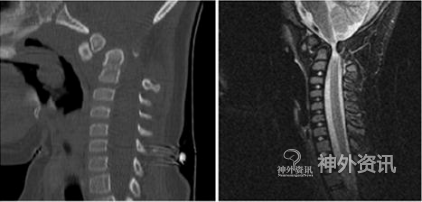

病例1. 12岁女孩,21-三体综合征。6年前有摔倒受伤史,当时无明显不适。但数月后出现左侧肢体进行性肌力减退,行走和言语困难。8岁时曾行枕骨-颈4融合术,术后运动和认知功能改善,但因枕部固定失效和感染,于10个月后去除固定装置,之后患者的症状逐渐加重。CT显示颈椎严重畸形,齿状突明显移位;MRI发现脑干受压严重并伴有脊髓信号改变(图2)。因病情不再适合做原位融合,故选择给予穿戴Halo背心牵引系统,使用4周,最大牵引力达到18磅。之后患者颈椎畸形明显改善。随后,作者进行枕骨大孔减压术和枕骨-C5融合术。由于椎动脉在左侧走形弯曲,遂在颈2水平仅对右侧椎弓根螺钉固定。术后CT扫描示腹侧脑干受压的现象得到纠正;患者的神经和运动功能明显改善,已能独立行走。CT随访显示颈部固定良好(图3)。

图2. 左图:CT矢状位示严重移位的齿状突;右图:MRI-T2像示脑干重度受压。